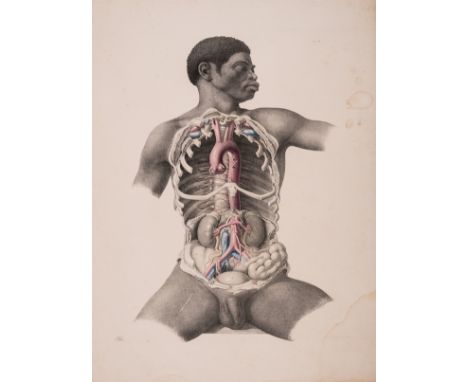

Anatomy.- Tortebat (François) Abregé d'Anatomie, accomodé aux Arts de Peinture et de Sculpture, second edition, engraved pictorial title, 10 engraved full-page illustrations after Vesalius, some spotting and light marginal staining, old marbled wrappers, a little rubbed and stained, spine repaired, preserved in modern cloth folder and slip-case, Paris, J.B.Crepy, 1760; and an Atlas of 13 engraved plates illustrating Scarpa's anatomy (4 with partial hand-colouring), folio (2)⁂ The second most important work on anatomy for the use of artists, first published in 1667 and preceded only by van der Gracht's Anatomie... of 1634. The plates are taken from Vesalius, re-engraved and reversed, and feature male figures as skeletons or displaying their muscles, tendons, etc.

Anatomy.- Tuson (Edward William) Myology..., 2 vol. in1 including Supplement, vol.1 second edition, Supplement first edition, lacking title to vol.1 (supplied in facsimile), with a total of 17 hand-coloured lithographed plates with multiple flaps, each with explanatory leaf of text, plate 1 lacking flap A from figure 2, one or two others possibly lacking, dedication very soiled and stained with small tear repaired, some spotting and soiling to plates and offsetting to text, modern half calf over marbled boards, spine gilt with red morocco label, large folio, 1828; sold not subject to return⁂ Complex teaching atlas with superb plates printed by Hullmandel, some with numerous flaps to simulate dissection. Tuson was a protégé of Astley Cooper and succeeded Charles Bell as surgeon at the Middlesex Hospital.

Anatomy.- Maclise (Joseph) Surgical Anatomy, first edition, 35 lithographed plates with partial hand-colouring by Hanhart after Maclise, some light spotting and marginal water-staining, a few with tears at edges (some repaired), loose with the original printed upper wrappers of the 9 original parts in modern cloth portfolio with ties, folio, 1851.⁂ Rare with the original part wrappers.